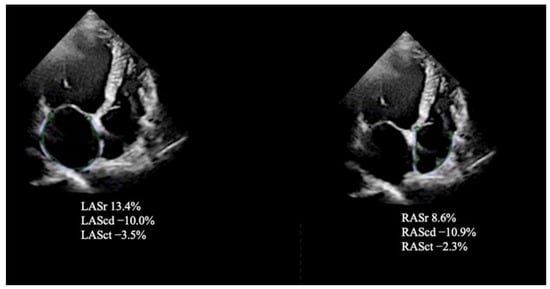

| LAScd, % | −10.7 ± 3.2 | −16.0 ± 4.1 | <0.001 |

| LASr, % | 19.1 ± 6.1 | 27.4 ± 6.0 | <0.001 |

| LASct, % | −8.1 ± 2.6 | −11.6 ± 4.9 | <0.001 |